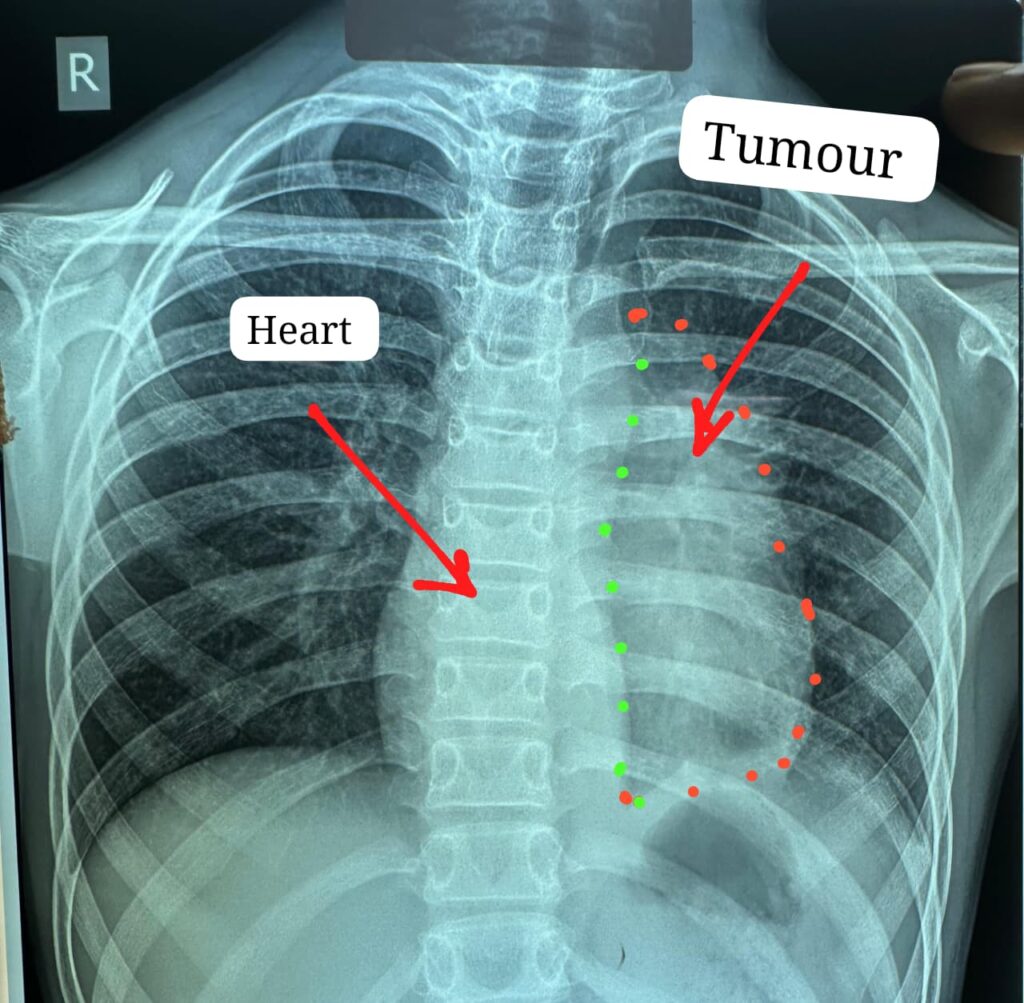

स्टेज-3 इनवेसिव थायमिक कैंसर का सफल ऑपरेशन; अब तक मेडिकल जर्नल में 12 वर्ष के सबसे कम उम्र का मरीज है , यह ट्यूमर (इनवेसिव थाइमोमा) सामान्यतः 40 से 60 वर्ष के लोगों में होता है ट्यूमर ने हार्ट के साथ, पेरिकार्डियम, फ्रेनिक नर्व,महाधमनी, मुख्य पल्मोनरी आर्टरी(एमपीए), लेफ्ट एट्रियम एवं फेफड़े को अपनी चपेट में ले रखा था

डॉक्टरों के अनुसार यह ट्यूमर सामान्यतः 40 से 60 वर्ष के लोगों में पाया जाता है और बच्चों में इसका मिलना अत्यंत दुर्लभ है। यह ट्यूमर हृदय, पेरिकार्डियम, फ्रेनिक नर्व महाधमनी (एओर्टा), मुख्य पल्मोनरी आर्टरी, लेफ्ट एट्रियम और फेफड़े से चिपका हुआ था। ऐसे मामलों में ट्यूमर को पूरी तरह निकाल पाना (आर-0 रिसेक्शन) लगभग असंभव माना जाता है, लेकिन अस्पताल में उपलब्ध हार्ट-लंग मशीन की मदद से यह संभव हो पाया।

मुख्य ट्यूमर के अलावा फेफड़े की प्लूरल कैविटी में फैले तीन अन्य सैटेलाइट ट्यूमर को भी सावधानीपूर्वक निकाला गया, ताकि भविष्य में कैंसर दोबारा फैलने की संभावना न रहे। निकाले गए ट्यूमर का आकार लगभग 12×8 सेंटीमीटर और वजन करीब 400 ग्राम था।